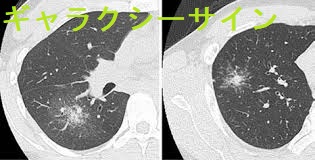

胸部CTでは他に、胸膜側のリンパ路に沿った多発粒状影や、ギャラクシーサイン(粒状影が集簇して結節を形成)を認めます。肺結核やMALTリンパ腫などでも見られます。(Sarcoidosis Vasc Diffuse Lung Dis. 2016 Oct 7;33(3):247-252.)